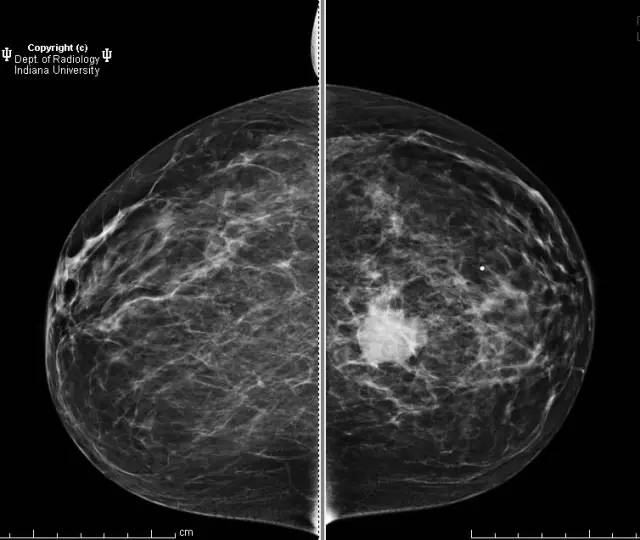

乳腺钼靶左乳腺内上象限见3.1cm卵圆形等密度肿块,部分界限清晰。超声见一2.5 x 2.1 x 1.9 cm混合回声肿块,宽大于高,边界清晰,后部回声增强。

浸润性导管癌

Invasive ductalcarcinoma